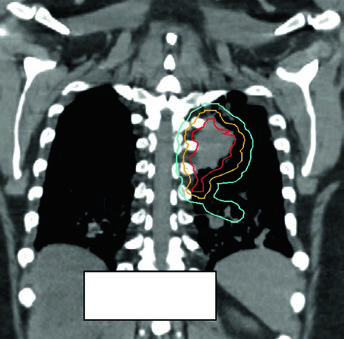

Replanejamento adaptativo: quando a anatomia muda durante o tratamento

Tumores obstrutivos que causam atelectasia podem resolver parcialmente durante o tratamento à medida que a radioterapia reduz o volume tumoral e o pulmão reaeração. Esse fenômeno, documentado nas CBCT de verificação, pode expor tecido pulmonar previamente colapsado à dose prevista para o tumor, alterando dramaticamente a distribuição de dose.

O replanejamento adaptativo deve ser considerado quando a CBCT mostra mudança anatômica significativa — expansão pulmonar ipsilateral, redução de derrame ou colapso em resolução. O caso da Figura 13.7 ilustra uma lesão metastática tratada com 45 Gy/15fx: a reaer ação pulmonar durante o tratamento exigiu replanejamento para proteger o pulmão recém-arejado.

Não existe protocolo universal para o gatilho do replanejamento adaptativo. Na prática, CBCT semanal com revisão pelo planificador e pelo oncologista é o mínimo razoável. Qualquer mudança visual significativa no contorno pulmonar ou mediastinal justifica recalcular os DVHs antes de continuar.